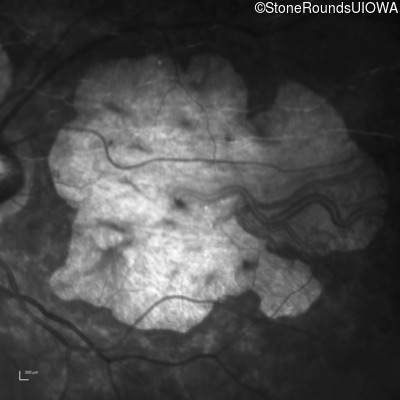

Infrared Fundus Photograph - Left - 20/150

Exemplar